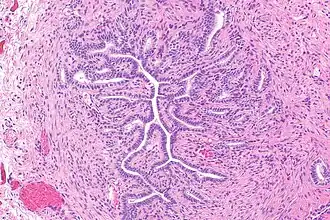

Gartner's duct, also known as Gartner's canal or the ductus longitudinalis epoophori, is a potential embryological remnant in human female development of the mesonephric duct in the development of the urinary and reproductive organs.[2] It was discovered and described in 1822 by Hermann Treschow Gartner.

Gartner's duct is located in the uterus' broad ligament. Its position is parallel with the lateral uterine tube and lateral walls of vagina and cervix.

These may give rise to Gartner's duct cysts.[3]